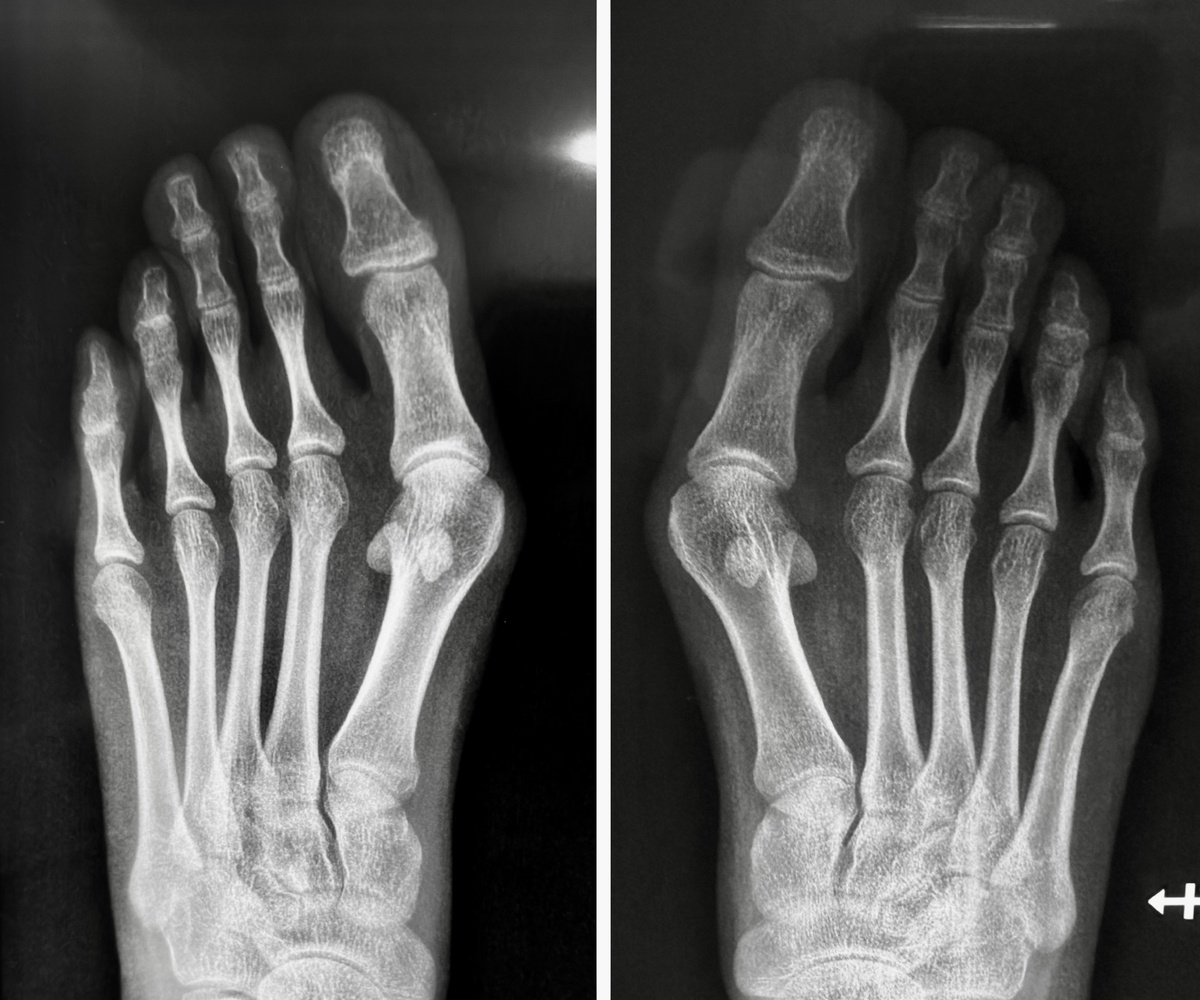

Заботливая и беспокойная мама читает меня, и обратилась с другой проблемой - «шишками»/«косточками» на стопах. Прислала рентгенограммы, всё обсудили на видеоконсультации, запланировали исправить деформацию обеих стоп.

Всё очевидно, вопросов нет. Если такая деформация в 19, очевидно, что дальше будет только хуже.

И вот тут начинается интересное. Смотрю девчушку. Да, деформация переднего отдела очевидна, да, нуждается в хирургической коррекции. НО: есть то, чего не видно на рентгене, а именно - вальгусная установка стоп. Крайне важная вещь!

При такой картине ставить на место первые пальцы - совершенно пустая затея. Организм сделает всё, чтобы вернуть пальцы и головки первых плюсневых костей обратно - тело пытается создать точки опоры, что запускает патологический процесс.